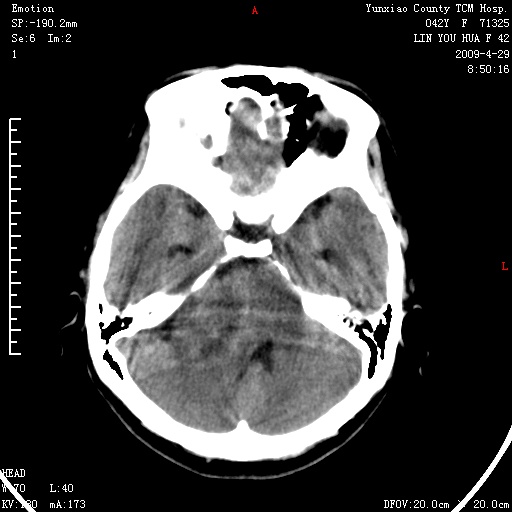

标题: CT19697:反复视物模糊半年,双眼视乳头轻度水肿 [打印本页]

右侧桥小脑角区肿瘤,高密度囊变有显著强化,骨窗见内听道显著扩大,考虑听神经瘤可能性大

1)右侧听神经瘤。2)阻塞性脑积水。